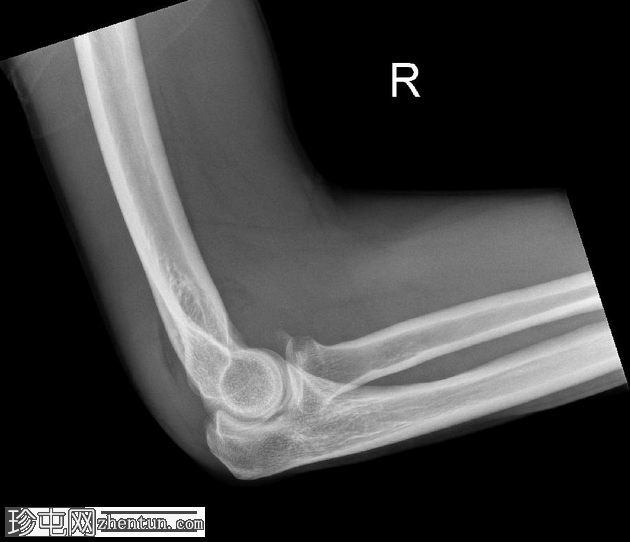

1.png

斜位片

桡骨头关节内粉碎性骨折,关节面轻微凹陷。肱骨远端前侧可见移位的骨碎片,桡骨头位片上清晰可见。可见前后脂肪垫征,提示肘关节积液。

未见肘关节脱位,肱桡骨小头排列保持正常。冠突水平可见复合阴影,可能与软组织重叠或投影伪影有关。桡骨和尺骨骨干外观完整,无骨折征。周围软组织肿胀。